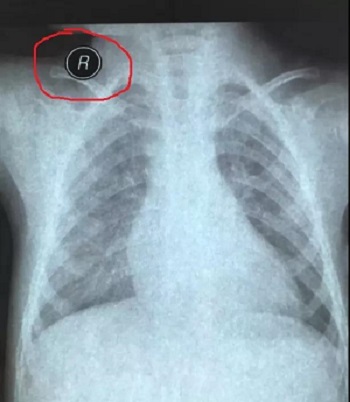

十二、拍摄时,尽可能的将片子上的文字信息拍摄清楚,并将左右拍摄清楚(片子上有标R,表示右侧right,L, 表示左侧left的意思), 每张片子上的文字都能按照阅读习惯拍正确,不要拍反了。

拍摄时,必须要对着片子上的文字对焦, 方向正确,将文字拍摄得清晰可视,保证放大图片后文字依然清晰可见(如下图),尽可能多的保留片子上的信息。